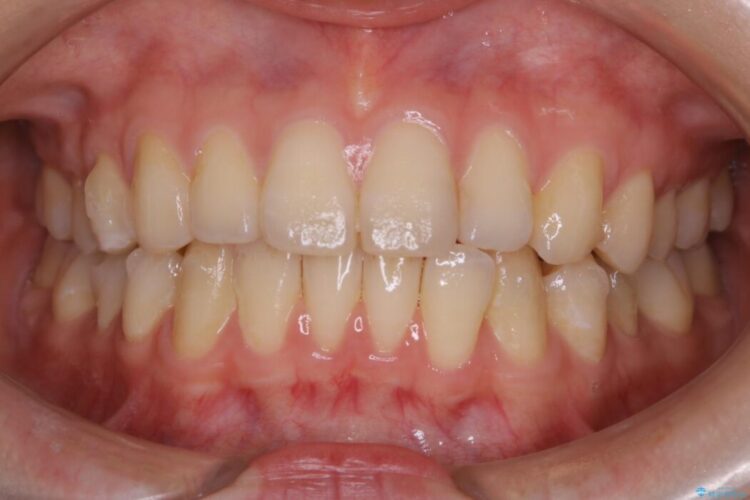

下の前歯のガタつきが気になるとご来院された患者様です。

インビザラインのライトパッケージにて、歯列拡大とディスキング(IPR)をを行いスペースをつくり非抜歯で治療を行いました。